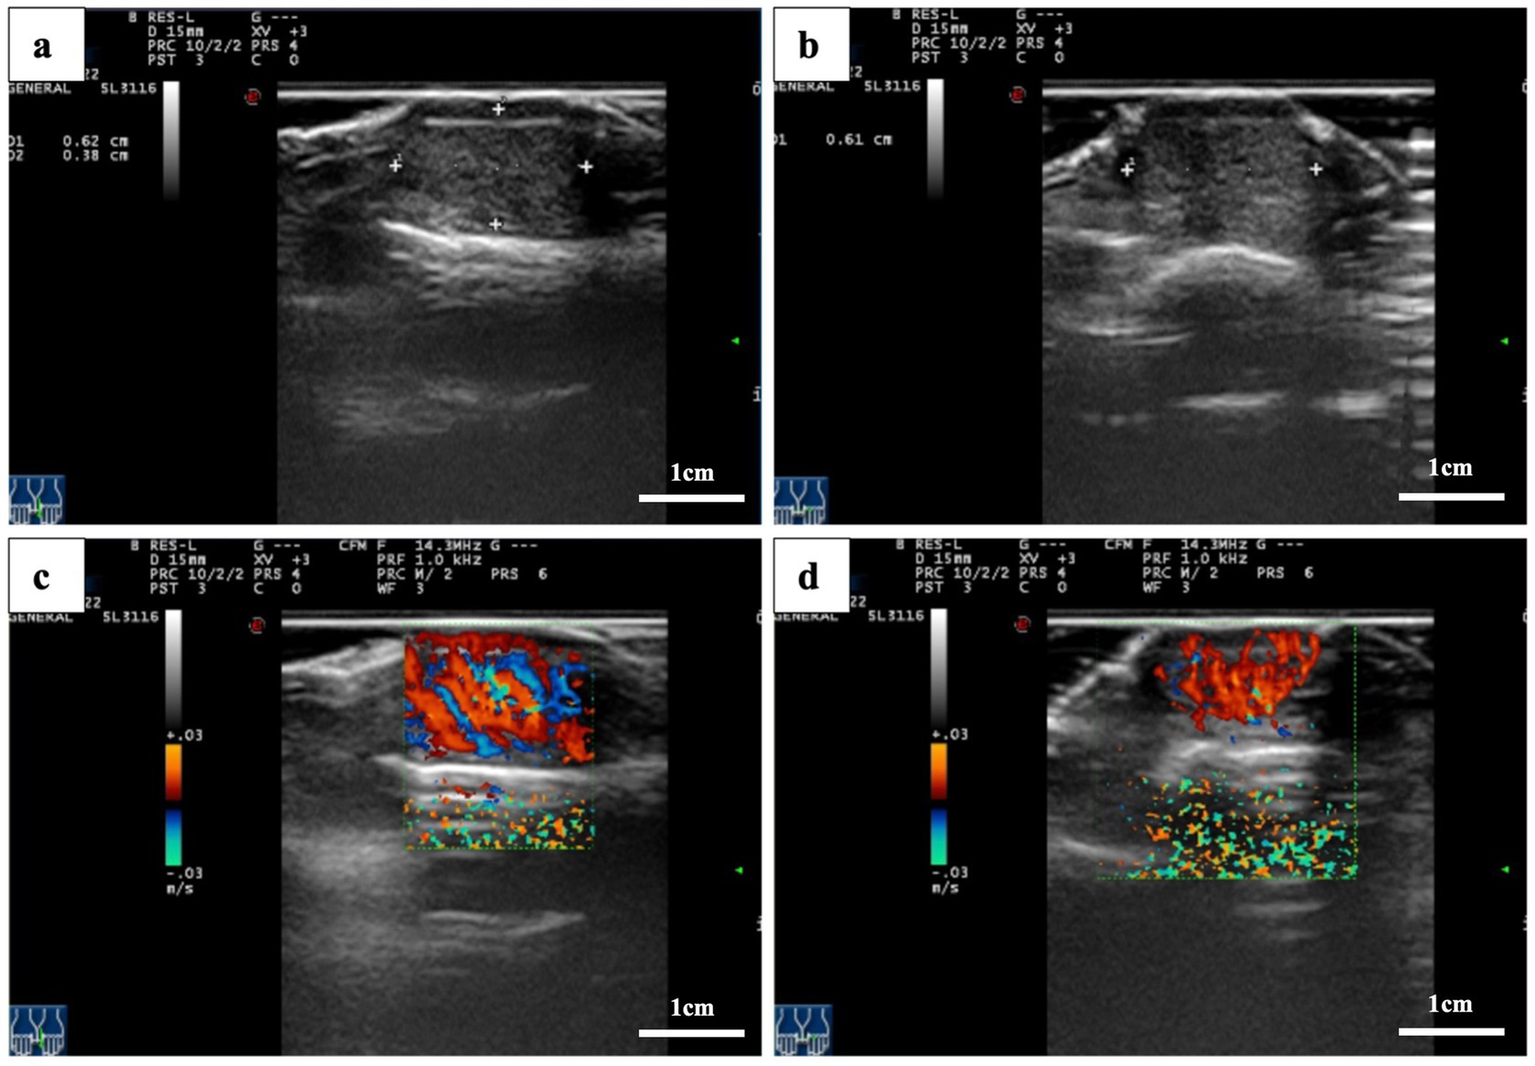

Magnetic resonance imaging (MRI) of the left hand revealed a flaky abnormal signal shadow on the dorsal side of the first distal phalanx. The lesion was low to moderate signal on T1-weighted imaging (T1WI), high signal on T2-weighted imaging (T2WI), and T2 fat suppression sequences (FSE) with well-defined borders. High signal with poorly defined borders on DWI sequences. The surrounding soft tissue was edematous, but there was no obvious destruction of the bone (Figure 2). High-frequency ultrasonography (14.3 MHz) revealed a well-defined low-echo nodule measuring approximately 0.62 × 0.38 × 0.61 cm, exhibiting highly abundant blood flow signals in color Doppler flow imaging (CDFI) (Figure 3).

Figure 3

Ultrasound images. (a,b) A hypoechoic nodule with well-defined borders is located beneath the thumbnail. (c,d) Color Doppler flow images showing nodular microvascular enrichment.

In contrast, high-frequency ultrasound may provide superior resolution in this case. Ultrasound provides high spatial resolution for superficial lesions and allows real-time evaluation of tumor vascularity using CDFI. Upon reviewing and analyzing the images, we observed that extremely hypoechoic areas of the tumor based on two-dimensional images, with CDFI demonstrating pedicle-like vascular flow signals. These findings suggest an unbalanced and disorganized tumor blood supply, which is more characteristic of malignant lesions than benign subungual masses.

The main imaging differential in this case was subungual telangiectatic granuloma, a benign reactive lesion that arises secondary to chronic irritation, trauma, or infection (24, 25). This lesion typically appears hypervascular on Doppler imaging and hypoechoic on grayscale ultrasound. Due to these similarities, subungual amelanotic melanoma may be misdiagnosed as telangiectatic granuloma, particularly when pigmentation is absent. However, the presence of heterogeneous hypoechoic zones, irregular tumor margins, and pedicle-like vascular patterns can help differentiate melanoma from benign vascular lesions.